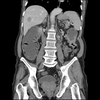

Paciente feminina, 48 anos, hipertensa e diabética tipo 2, com diagnóstico de neoplasia colorretal, submetida a tratamento cirúrgico e quimioterapia adjuvante há 8 meses. Durante o tratamento quimioterápico, apresentou importante perda ponderal, sendo seu peso atual de apenas 44 kg. Comparece ao pronto-socorro com queixa de epigastralgia, sensação de plenitude pós-prandial, saciedade precoce, náuseas e vômitos biliosos. Esses sintomas eram esporádicos, porém tornaram-se mais intensos nos últimos dias. Ao exame físico: descorada ++/4, desidratada ++/4, eupneica, afebril. FC: 98 bpm, PA: 110 x 60 mmHg, FR: 18 irpm. Abdome escavado, flácido, pouco doloroso à palpação e com distensão no andar superior, sem massas palpáveis, RHA presentes. Realizada passagem de sonda nasogástrica com saída de grande volume de estase gástrica. Exames laboratoriais: Hb: 9,5 g/dL; leuco: 10,50 mil/mm³ (sem desvio à esquerda); PCR: 10 mg/dL; K: 3,2 mmol/L, creatinina: 1,3 mg/dL; ureia: 40 mg/dL, glicemia: 163 mg/dL. Foi realizada tomografia contrastada de abdome (imagem a seguir). Em relação ao caso, qual é a principal hipótese diagnóstica?

Sindrome de wilkie, obstruindo o duodeno

46

O que é a sindrome de wilkie?

compressão da terceira porção do duodeno devido ao estreitamento do espaço entre a **artéria mesentérica superior** e a aorta